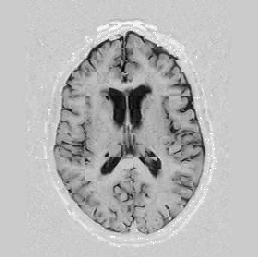

The last figure, Figure [*], shows an important comparison between two large registrations. Up to 20 knot-points were used.

Figure: Multi-scale NRR withsignificant knot-points increase. On the left, top then bottom: comprehensive NRR where everything is done at level 1; On the right:all at level 2.

In that last figure, there is a clear difference to be seen in terms of quality, notably in favour of the image on the left. It is a chequerboard image, but it may be hard to see it because the level of overlap is high. Consequently, this registration worked a lot better and my colleagues demonstrated that the overall framework worked fully, as the remainder of this section will describe.